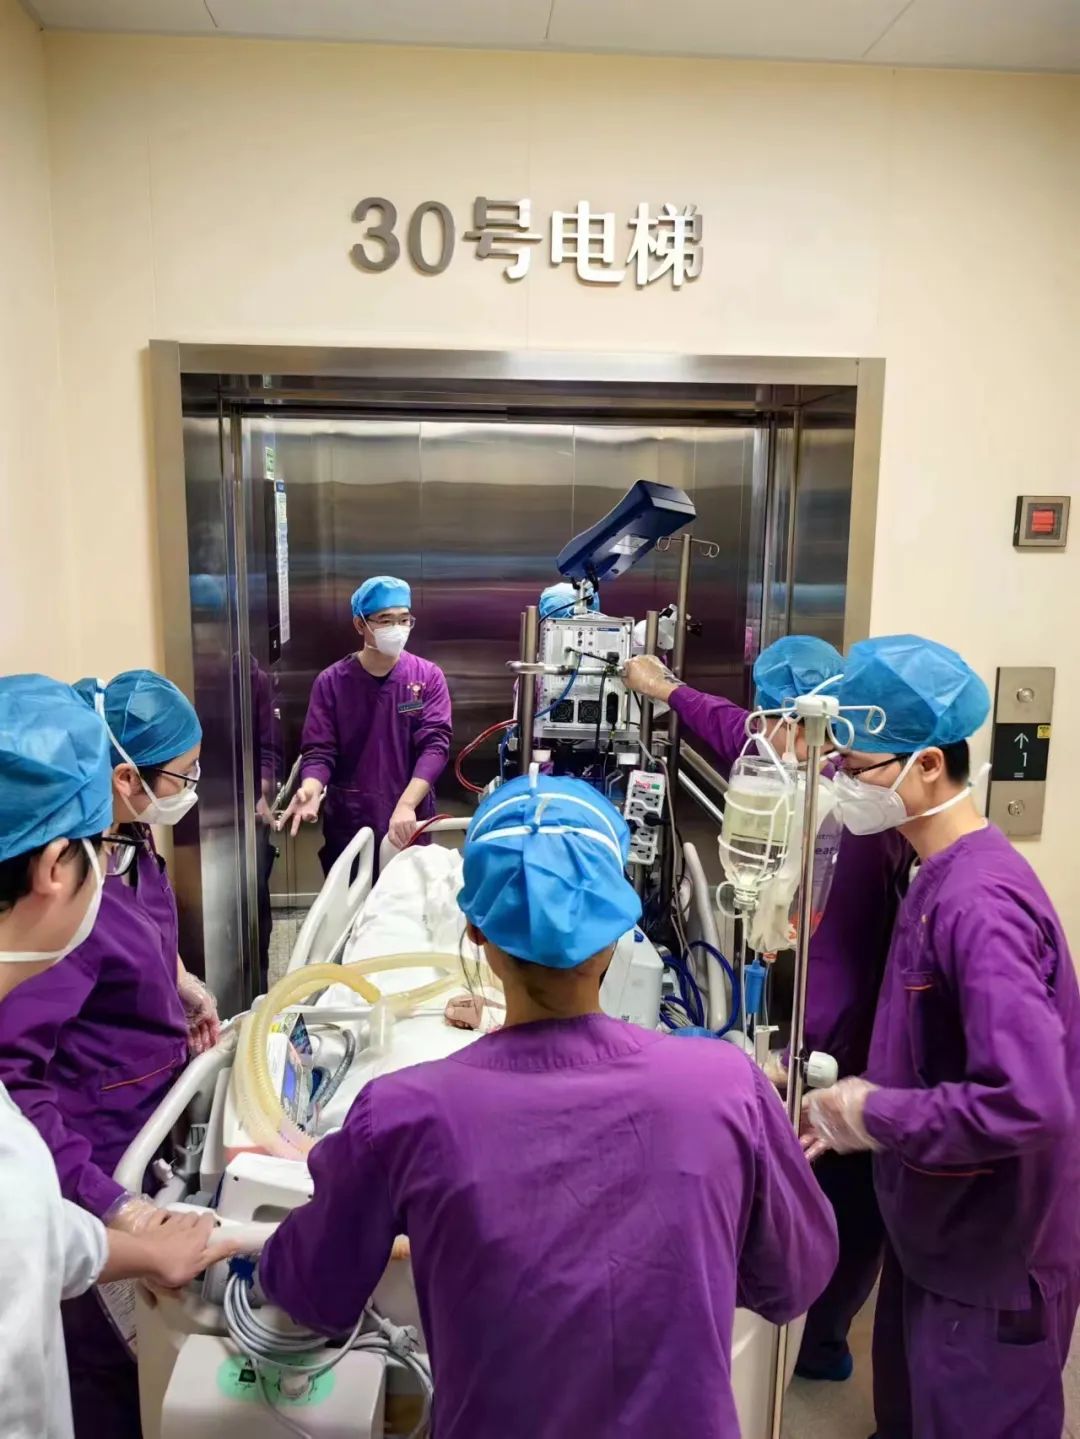

手术当天,心血管内科介入团队、ECMO团队、麻醉科、介入室等多学科团队相互接力,密切合作。重症医学科ECMO团队顺利建立血管通路、ECMO开机运转、麻醉等各项工作有条不紊进行。

ECMO 置管中

ECMO 置管中